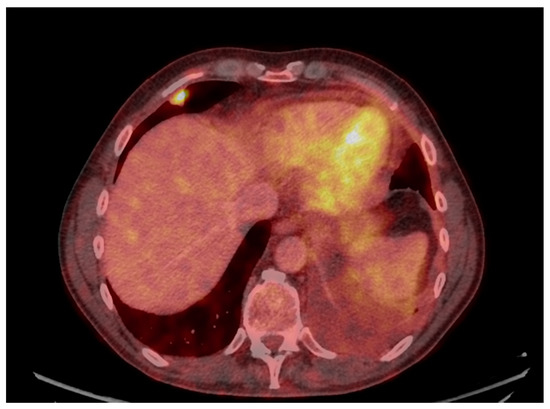

Uncommon Presentation of Granulomatosis with Polyangiitis Mimicking Metastatic Lung Cancer

3. Results